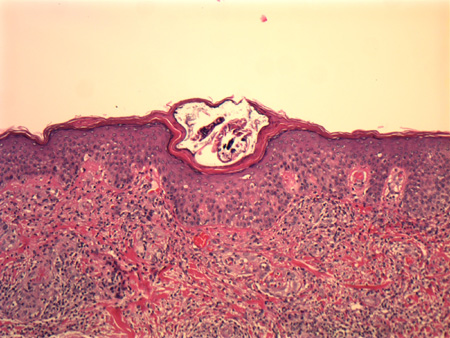

Skin biopsy may be done to look for an alternative diagnosis if ectoparasite is negative. However, it is rare to see a mite in the biopsy specimen, and the eosinophilic infiltrate seen in most biopsies is non-specific and not sufficient for diagnosis.[17][Figure caption and citation for the preceding image starts]: Histological section showing an adult Sarcoptes scabiei in its burrow in the stratum corneumFrom the collection of Pooja Khera, MD [Citation ends].

presence of mite, eosinophilic infiltrate; rarely, eggs and mite faecal material are found